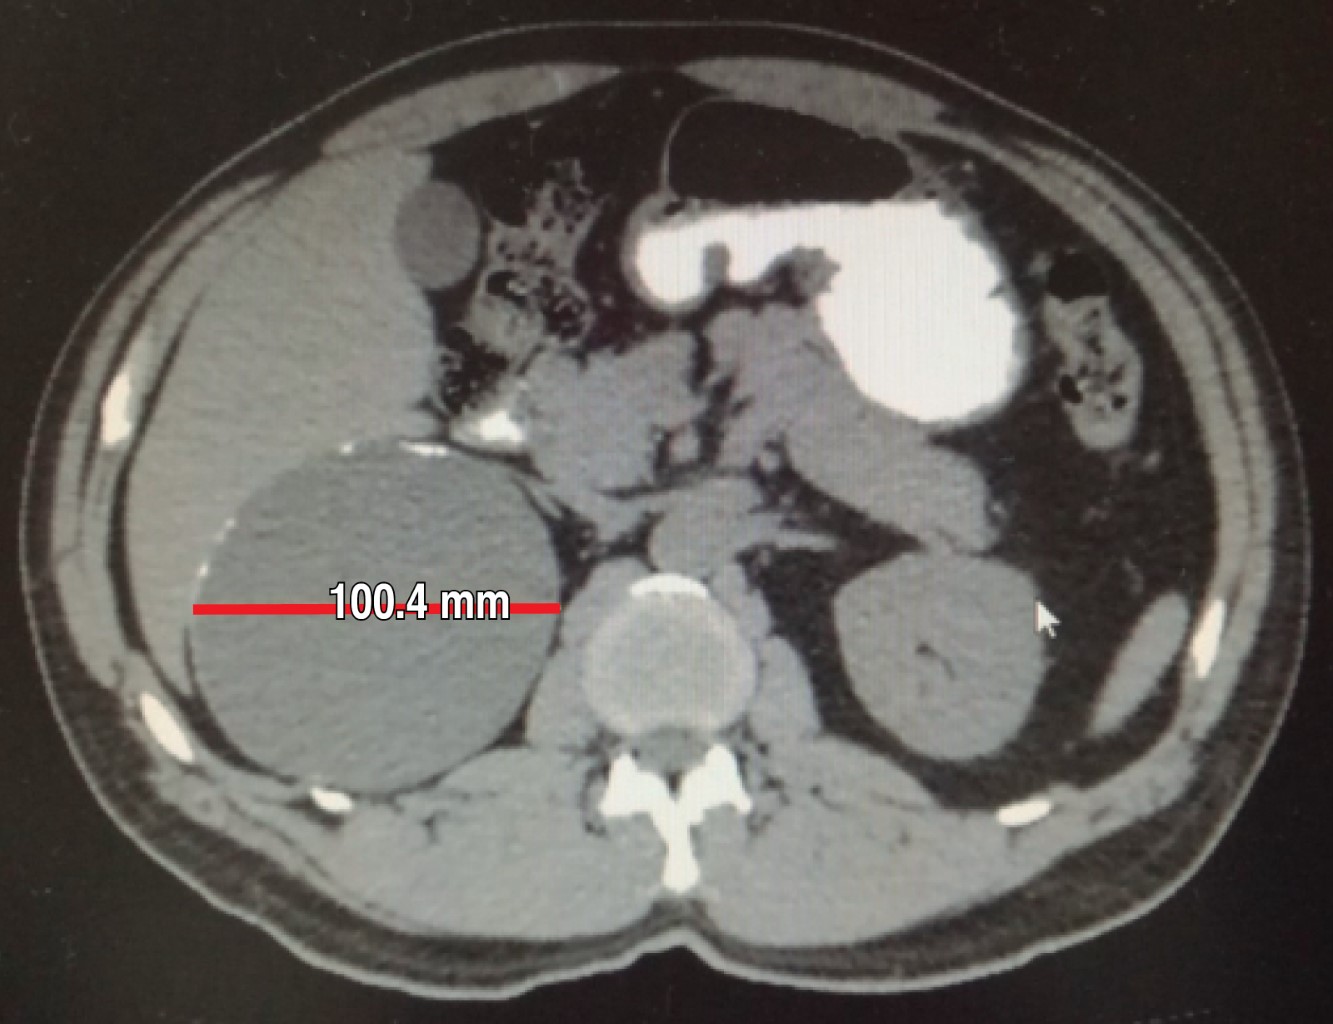

In May 2018 he had normal cytology blood cell counts, liver and renal function tests, and coagulation parameters. No cortisol, aldosterone, urinary catecholamine or metanephrine measurements were done. An abdominal CT scan performed in May reports a right adrenal gland hypodense image with a maximum diameter of 101 mm with calcification images inside it that was exerting occupational and compressive effect on surrounding structures (Figures 3, 4, 5 and 6). Once internal medicine service completed his preoperative assessment, an open anterior surgical approach was scheduled. He was given antibiotic prophylaxis with ceftriaxone 2 g in a single dose before a right subcostal incision was made and we proceeded to electrocautery removal of the right adrenal cyst of 10 × 9 cm. Adhesions to the liver were found and a content of approximately 400 ml of hyaline fluid and calcifications of about 20 × 40 mm in its interior were seen. A Penrose drainage of ½" (19 mm) was placed in the subphrenic space due to the suspicion of postoperative hemorrhage.

Figure 3

Figure 4